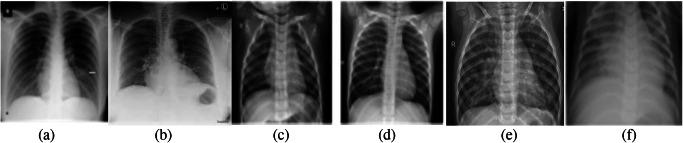

The quick spread of coronavirus disease (COVID-19) has become a global concern and affected more than 15 million confirmed patients as of July 2020. To combat this spread, clinical imaging, for example, X-ray images, can be utilized for diagnosis. Automatic identification software tools are essential to facilitate the screening of COVID-19 using X-ray images. This paper aims to classify COVID-19, normal, and pneumonia patients from chest X-ray images. As such, an Optimized Convolutional Neural network (OptCoNet) is proposed in this work for the automatic diagnosis of COVID-19. The proposed OptCoNet architecture is composed of optimized feature extraction and classification components. The Grey Wolf Optimizer (GWO) algorithm is used to optimize the hyperparameters for training the CNN layers. The proposed model is tested and compared with different classification strategies utilizing an openly accessible dataset of COVID-19, normal, and pneumonia images. The presented optimized CNN model provides accuracy, sensitivity, specificity, precision, and F1 score values of 97.78%, 97.75%, 96.25%, 92.88%, and 95.25%, respectively, which are better than those of state-of-the-art models. This proposed CNN model can help in the automatic screening of COVID-19 patients and decrease the burden on medicinal services frameworks.

冠状病毒病(COVID-19)的迅速传播已成为全球关注的问题,截至2020年7月,确诊患者已超过1500万。为了应对这种传播,临床成像,例如X光图像,可用于诊断。自动识别软件工具对于利用X光图像筛查COVID-19至关重要。本文旨在从胸部X光图像中对COVID-19患者、正常人和肺炎患者进行分类。因此,本文提出了一种优化卷积神经网络(OptCoNet)用于COVID-19的自动诊断。所提出的OptCoNet架构由优化的特征提取和分类组件组成。灰狼优化器(GWO)算法用于优化训练CNN层的超参数。利用一个公开可用的COVID-19、正常人和肺炎图像数据集,对所提出的模型进行了测试,并与不同的分类策略进行了比较。所提出的优化CNN模型的准确率、灵敏度、特异性、精确率和F1分数分别为97.78%、97.75%、96.25%、92.88%和95.25%,优于现有模型。所提出的CNN模型有助于自动筛查COVID-19患者,并减轻医疗服务系统的负担。